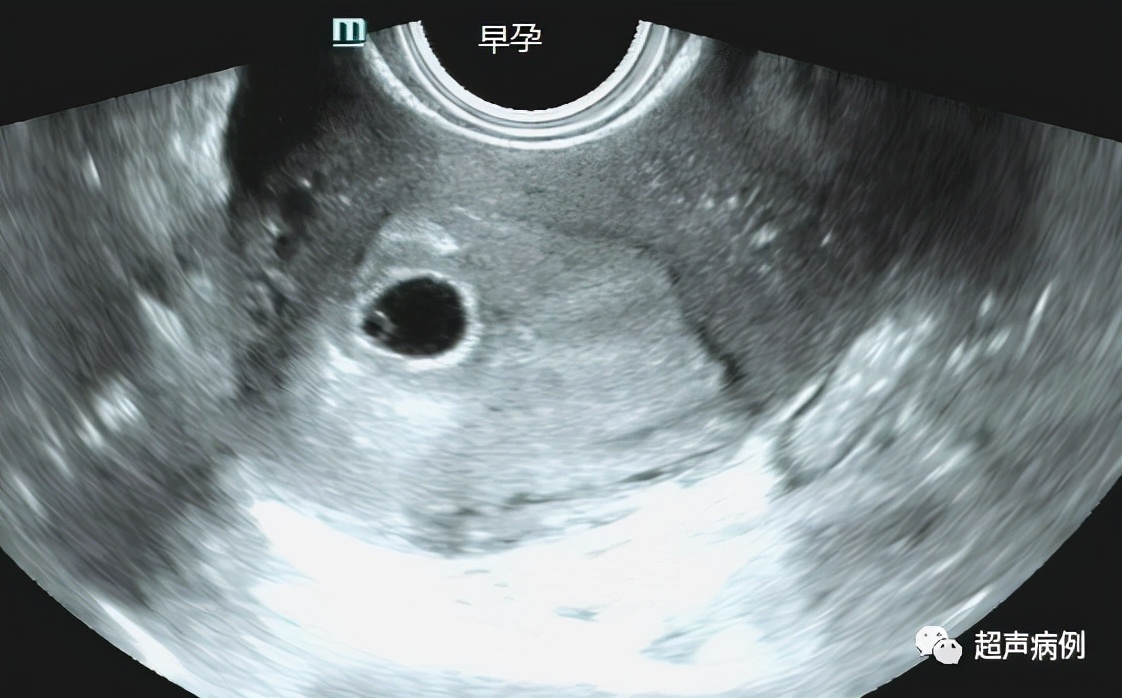

4、明确诊断早期妊娠(经腹无法观察的早孕);